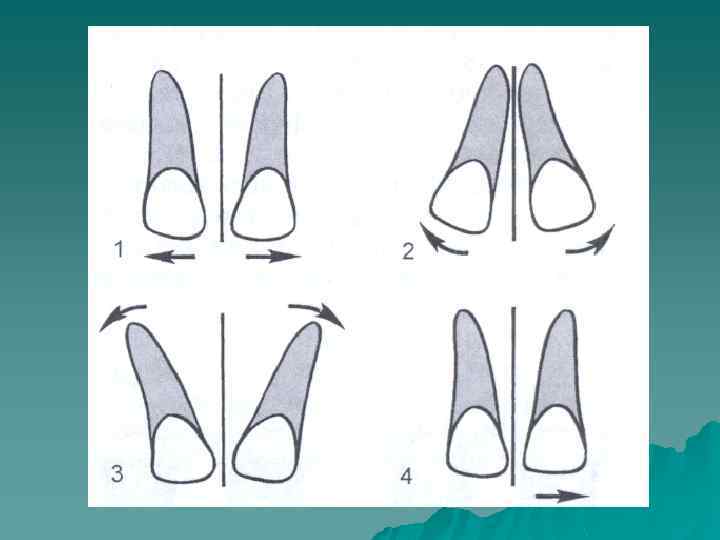

Различают следующие виды диастемы 1. 2. 3. 4. симметричная диастема - латеральное смещение центральных резцов; диастема, при которой наблюдается преимущественное перемещение коронок центральных зубов латерально от средней линии. Корни центральных резцов сохраняют свое положение или смещаются латерально незначительно; диастема, при которой коронки центральных зубов смещаются латерально от средней линии незначительно, а корни центральных резцов латерально значительно; асимметричная диастема, возникaющaя в том случае, когда один центральный резец смещается значительно латерально, а другой центральный резец сохраняет свое нормальное положение.

Необходимо отметить, что латеральное смещение центральных резцов может сочетаться с их поворотом по оси зуба (тортоаномалия) и смещением зубов по вертикали (зубоальвеолярное удлинение или укорочение).